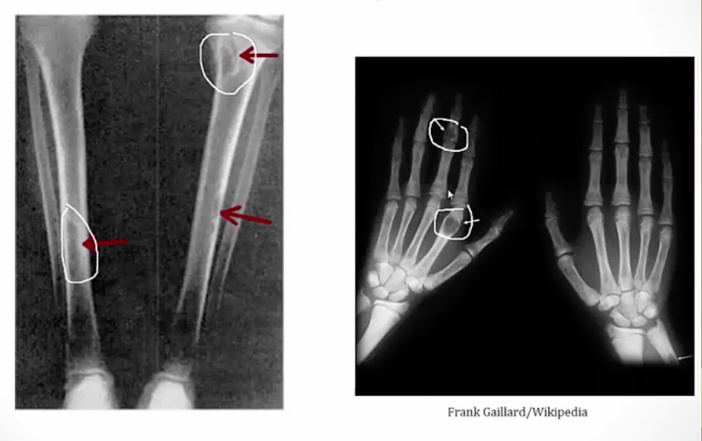

Osteitis Fibrosa Cystica

.,

Cystica means bone change

Periosteum: membrane surrounding the bone

_Histology shows fibrosis and bone spicules